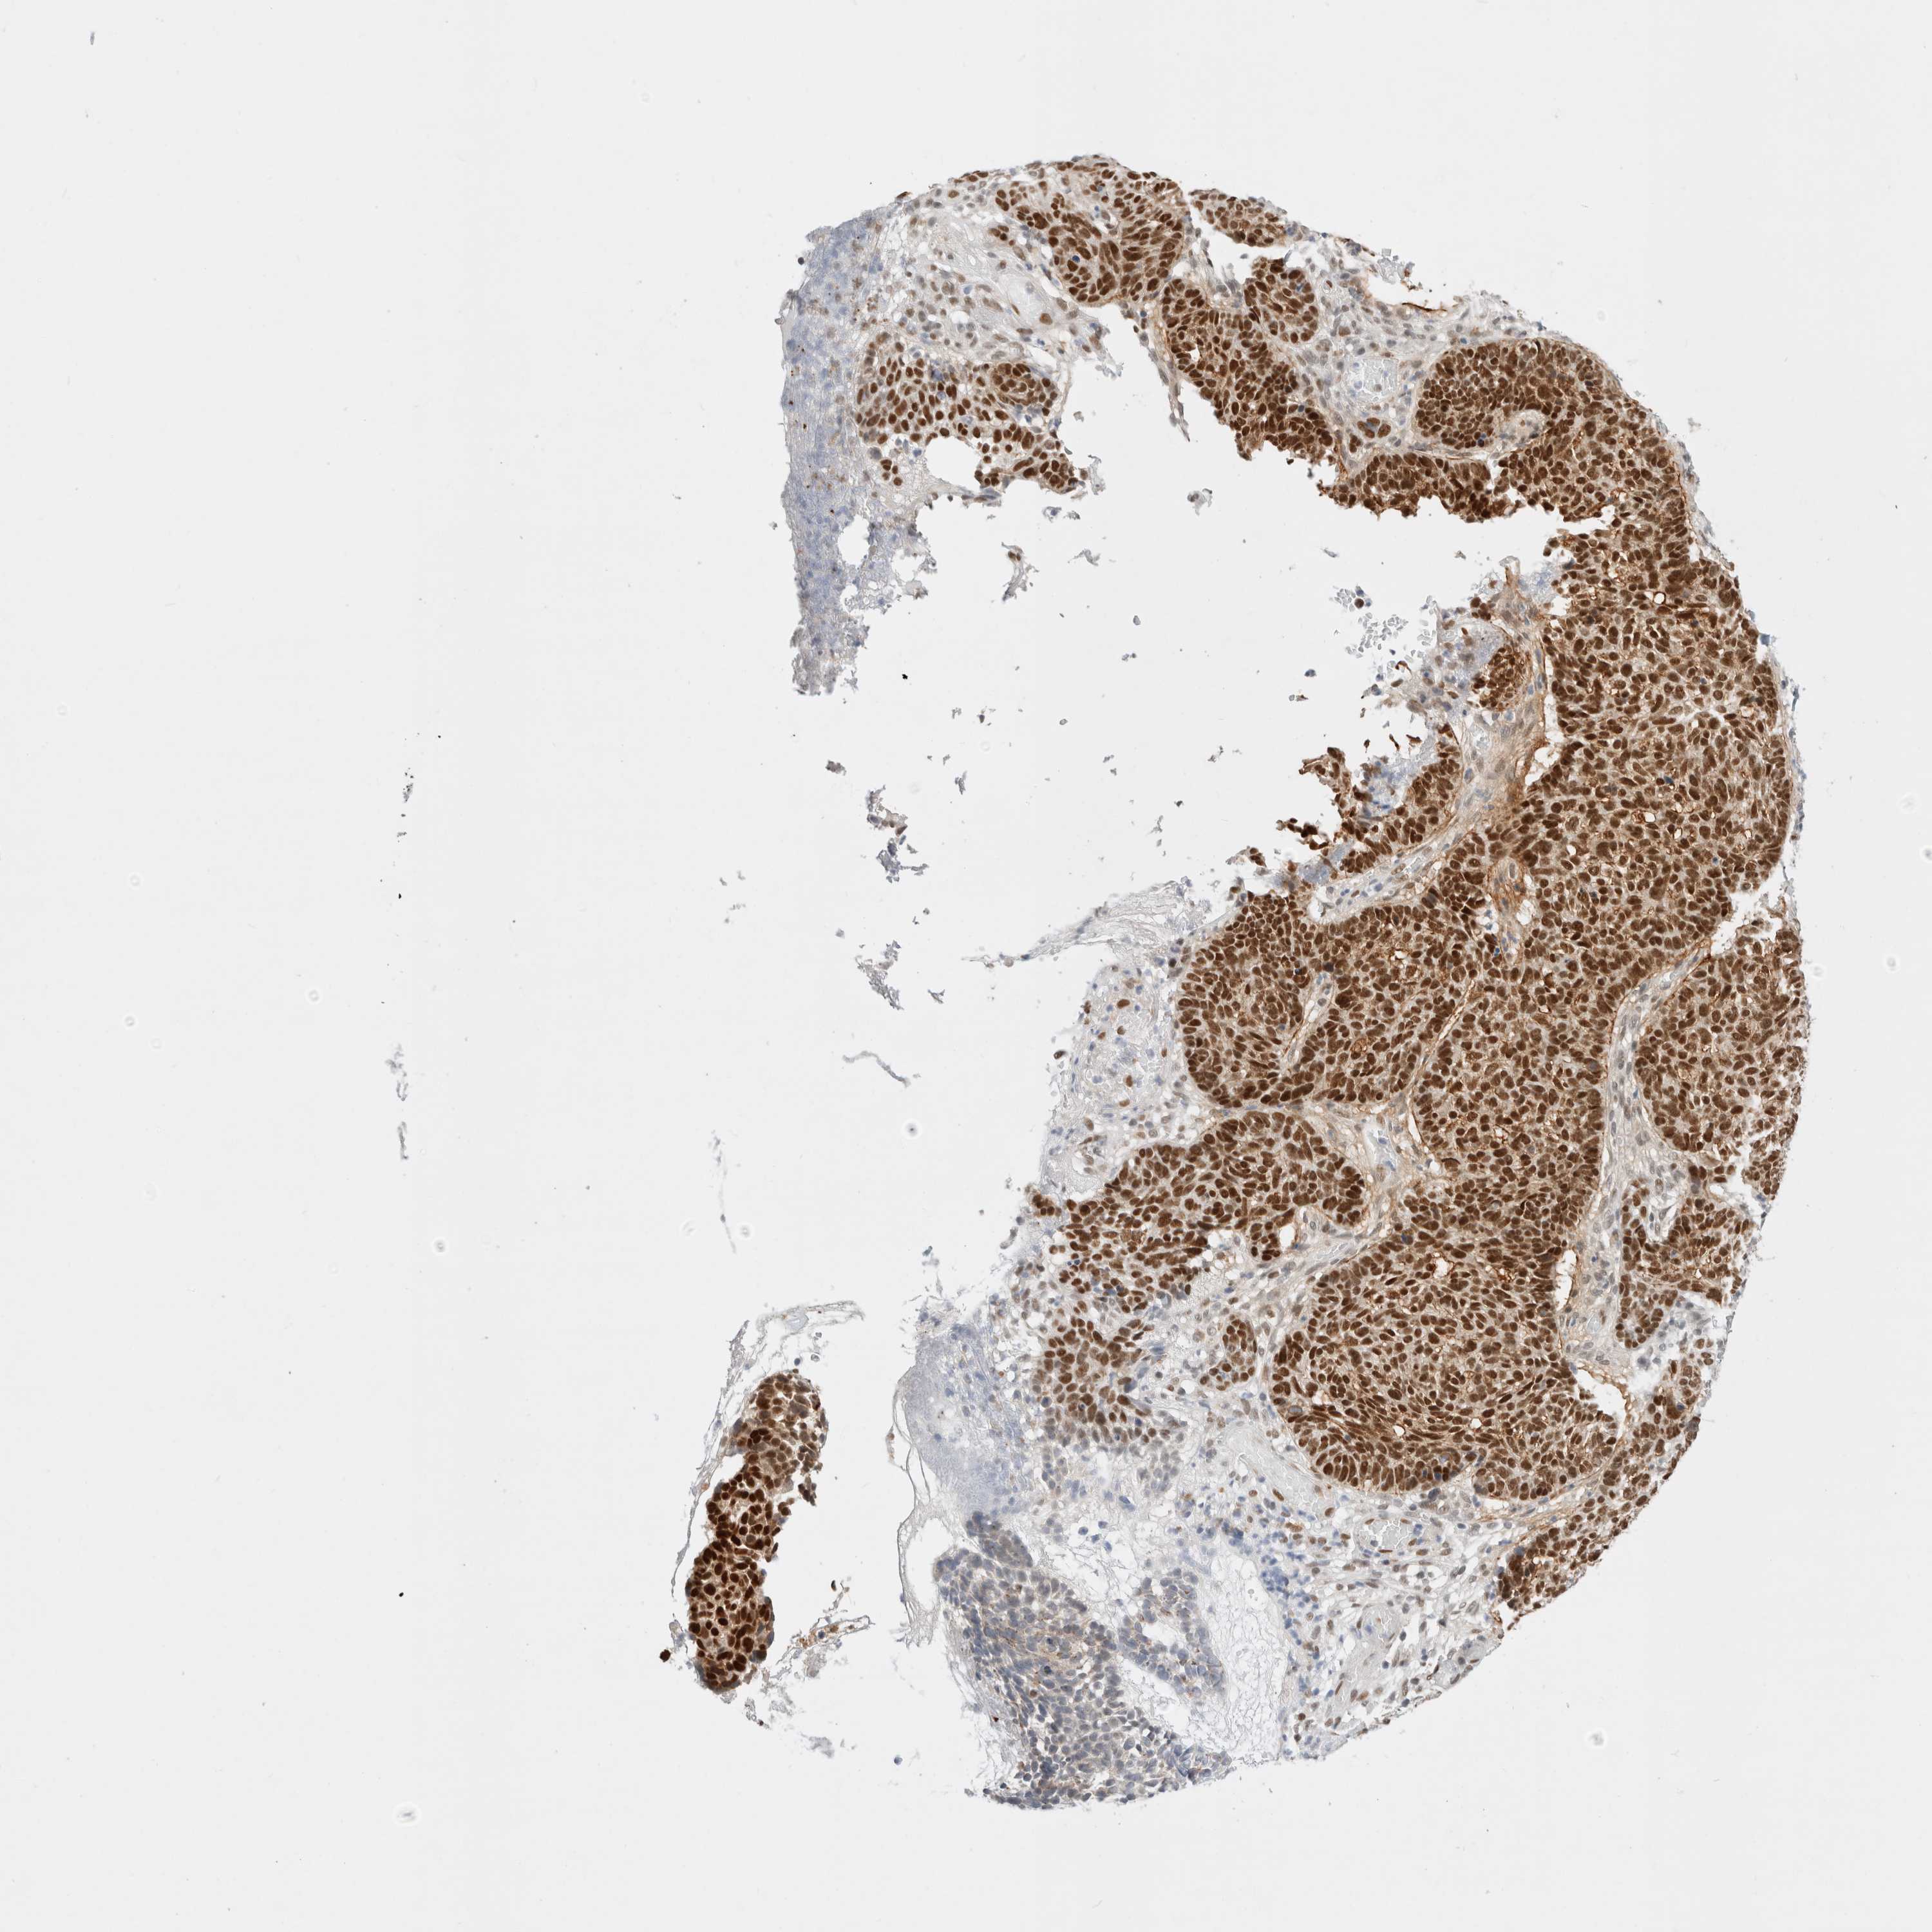

SKIN CANCER - Protein expressioni

A mouse-over function shows sample information and annotation data. Click on an image to view it in a full screen mode. Samples can be filtered based on level of antibody staining by selecting one or several of the following categories: high, medium, low and not detected. The assay and annotation is described here.

Antibody stainingi

Antibody staining in the annotated cell types in the current human tissue is reported as not detected, low, medium, or high, based on conventional immunohistochemistry profiling in selected tissues. This score is based on the combination of the staining intensity and fraction of stained cells.

Each image is clickable and will lead to virtual microscopy that enables deeper exploration of all samples and also displays staining intensity scores, fraction scores and subcellular localization as well as patient and tissue information for each sample.

Antibody CAB004595

Squamous cell carcinoma, NOS